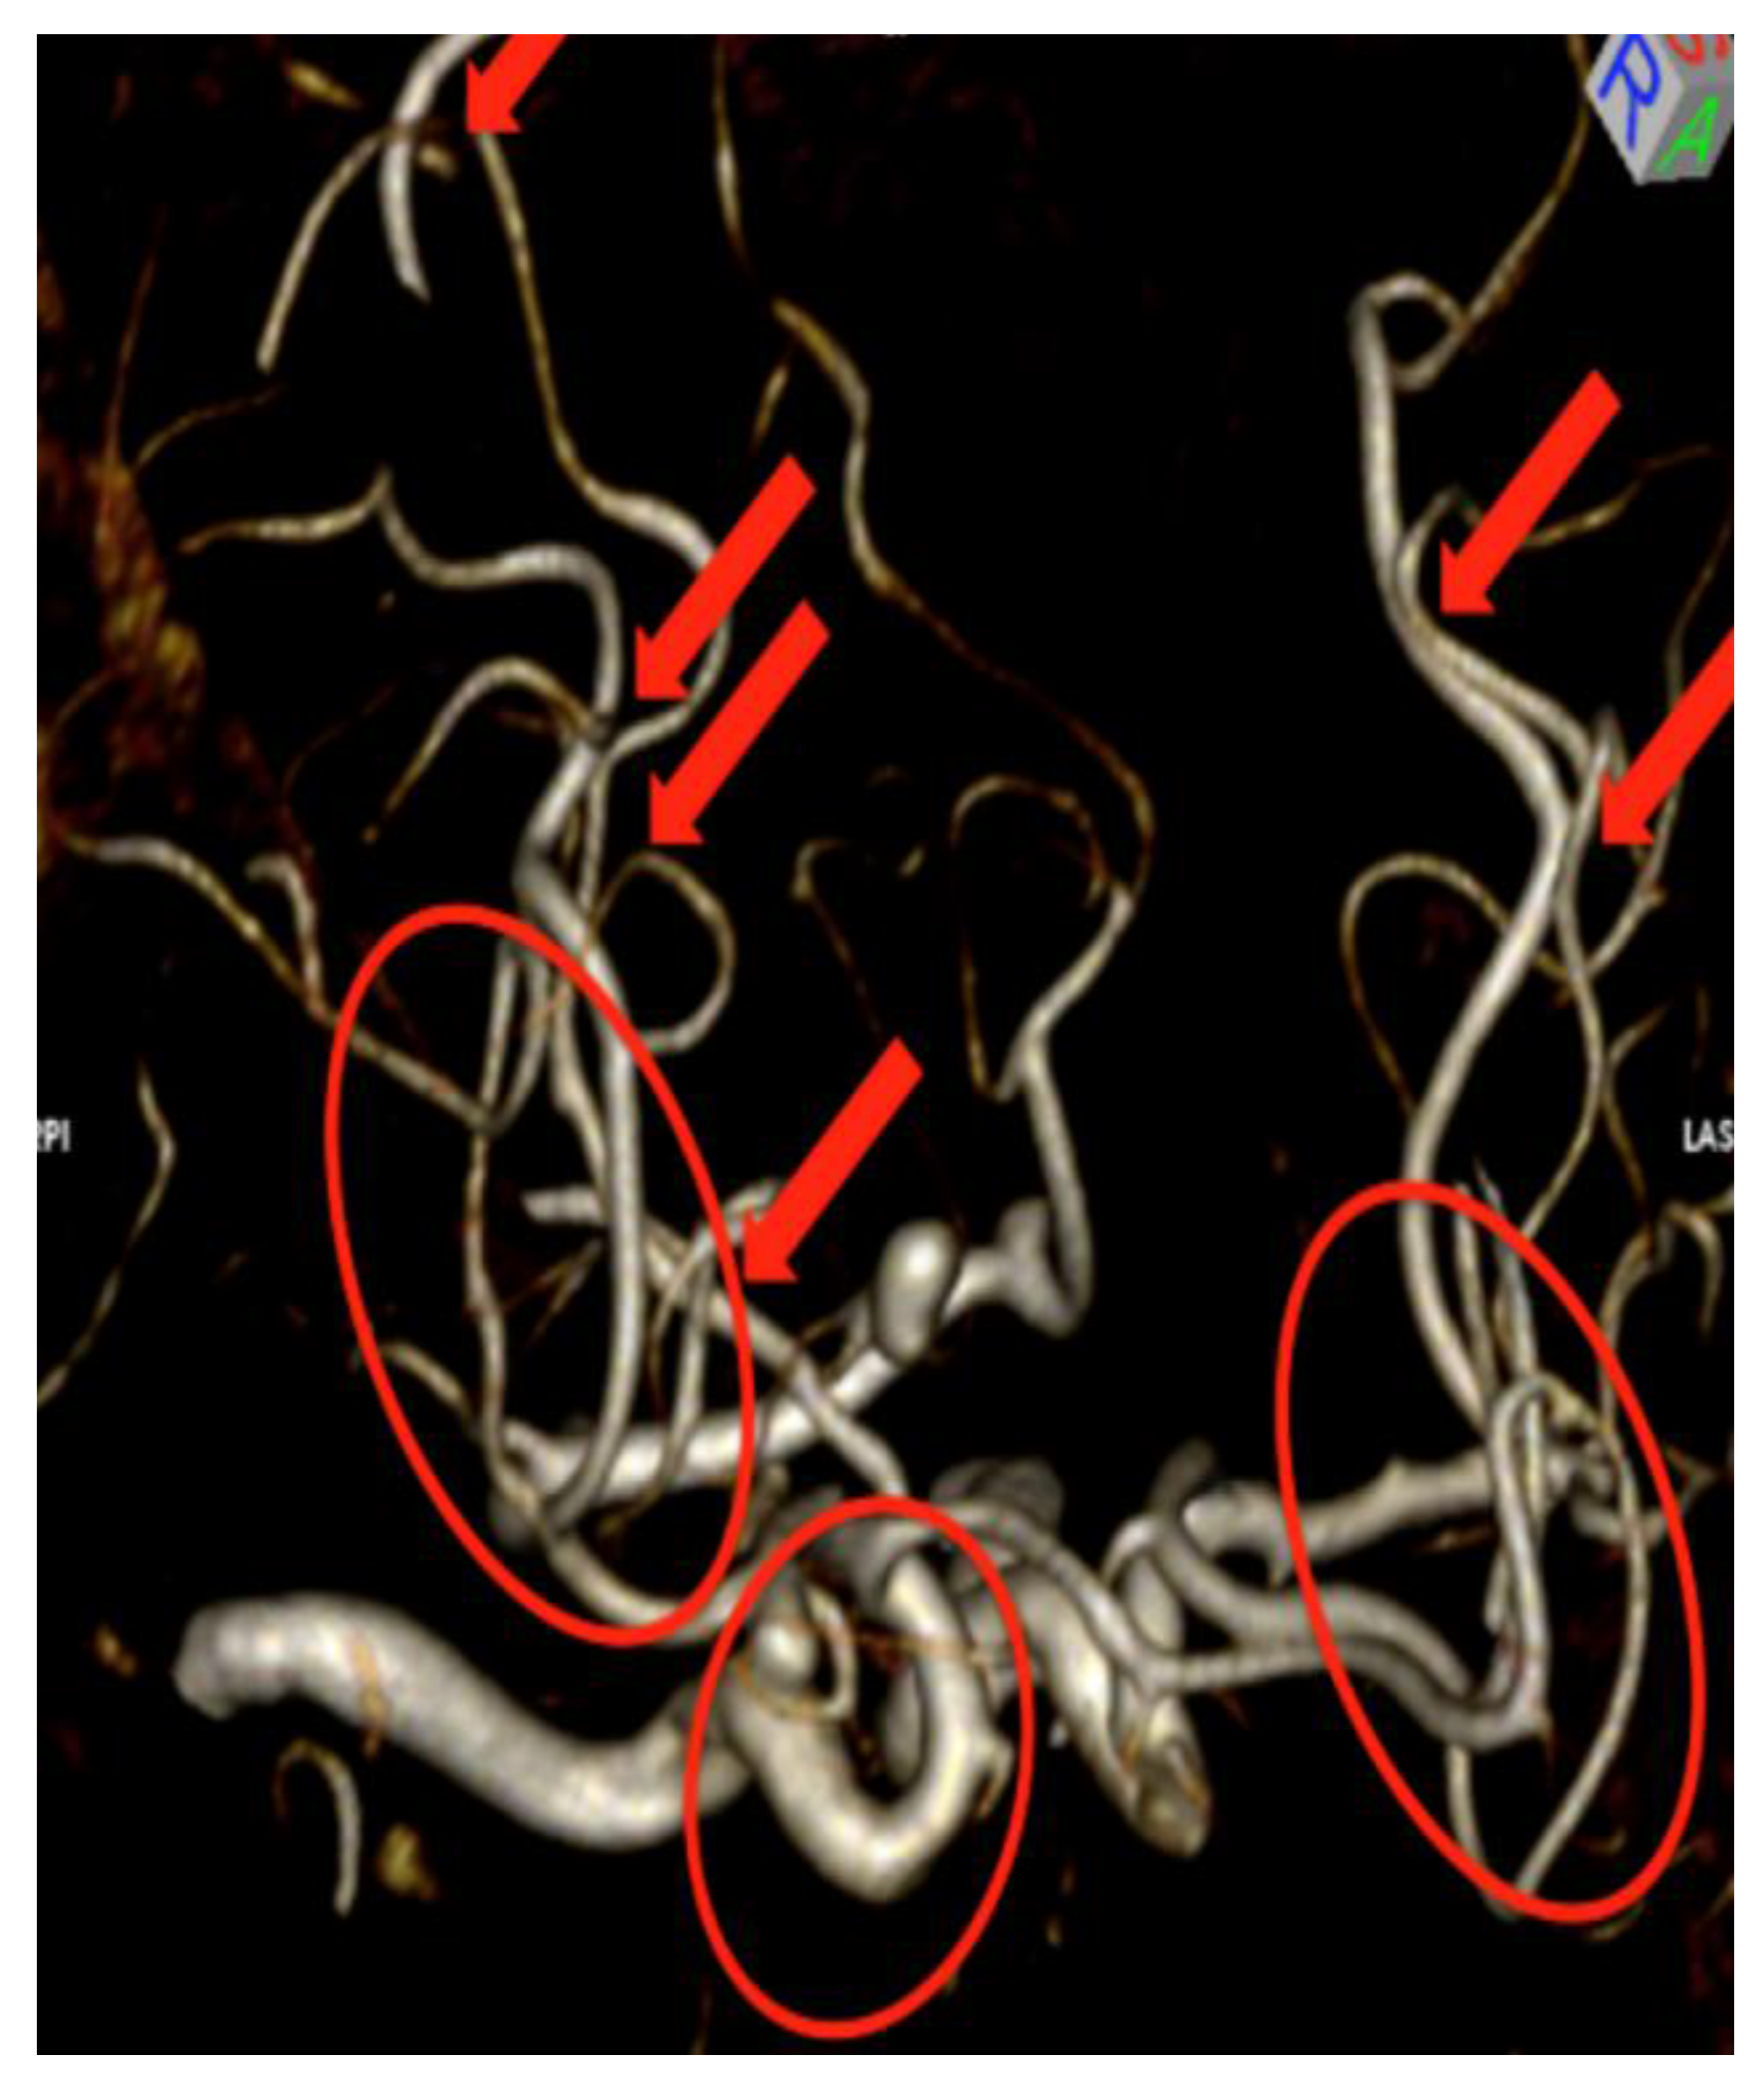

Figure 3.

Magnetic Resonance Angiography (MRA) viewed with a volume rendering technique shows the cerebral vasculature with all other tissues removed. Note that there are multiple areas of overlapping blood vessels as indicated by the red arrows and the red ovals. No matter which way the volume rendering image is rotated, overlapping vessels will be seen, which limits evaluation. Additionally, computer processing of the images is performed including an apparent light source and shadowing, which can potentially cause interpretation errors.

Fishman et al. and Johnson et al. have both documented advantages in displaying certain complex anatomical structures by volume rendering, but acknowledged the limitations due to overlapping anatomy [7,8]. There have been considerable efforts to overcome this limitation including importance-driven volume rendering [9], smart visibility [10] and curved planar reformation [11]. As one radiologist put it—“This is like looking at a bowl of spaghetti”. This radiologist prefers standard axial, sagittal and coronal plane imaging rather than volume rendering imaging for interpretation. The conclusion of many radiologists is that overlapping structures are difficult to visualize and leave an uneasy feeling among many radiologists as if they may be missing something that lies behind other structures. Typical displays for conventional volume rendering include high definition computer monitors.